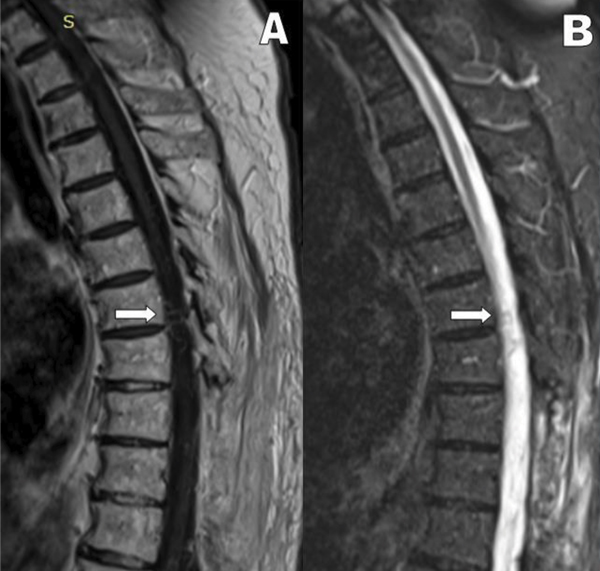

Por los antecedentes anteriormente mencionados y con el requerimiento de un centro de mayor complejidad, se decide la derivación a nuestra institución para su estudio. Al interrogatorio el paciente relata dolor lumbar y ciatalgia bilateral de más de 18 meses de evolución, con dificultades en la marcha, que progresaron hasta necesitar asistencia en silla de ruedas, agregando afectación esfinteriana en el último tiempo. Al examen físico, presentó paraparesia flácida severa, hiporreflexia tendinosa y nivel sensitivo desde T10. Se interpretó en un primer momento, por imágenes previas, como Mielomalacia en estudio. Por la evolución del cuadro clínico, se realizó en primera instancia una RMN dorsal con contraste endovenoso donde se observó realce vascular intracanal a nivel de D7 en secuencia T1 y un vaso serpinginoso en secuencia STIR (Figura 2). Se completó el estudio con Angiografía Vertebromedular donde se observó fístula arteriovenosa dural espinal (FAVd), que se origina a nivel de D7 izquierda, con gran congestión venosa a lo largo del canal (Figura 3). La Arteria Radicular Magna de Adamckievicz se localizó en L1 derecha. Se decidió realizar tratamiento quirúrgico por ser paciente con bajas comorbilidades, presencia de FAVd a nivel dorsal y reportes de alta tasa de éxito de la patología por microcirugía. Se realizó hemilaminectomia izquierda a nivel D7, localización de trayecto fistuloso a nivel foraminal, colocación de clip transitorio, coagulación con pinza bipolar y resección de fístula con microtijera (Figura 4). El paciente evolucionó con peoría de su patología renal de base e infección del tracto urinario lo que imposibilitó su control por imágenes posoperatorios.

Figura 2: RMN columna dorsal con contraste que muestra vaso serpinginoso a nivel D7 (flecha): A) Estudio en secuencia T1. B) Estudio en secuencia STIR.